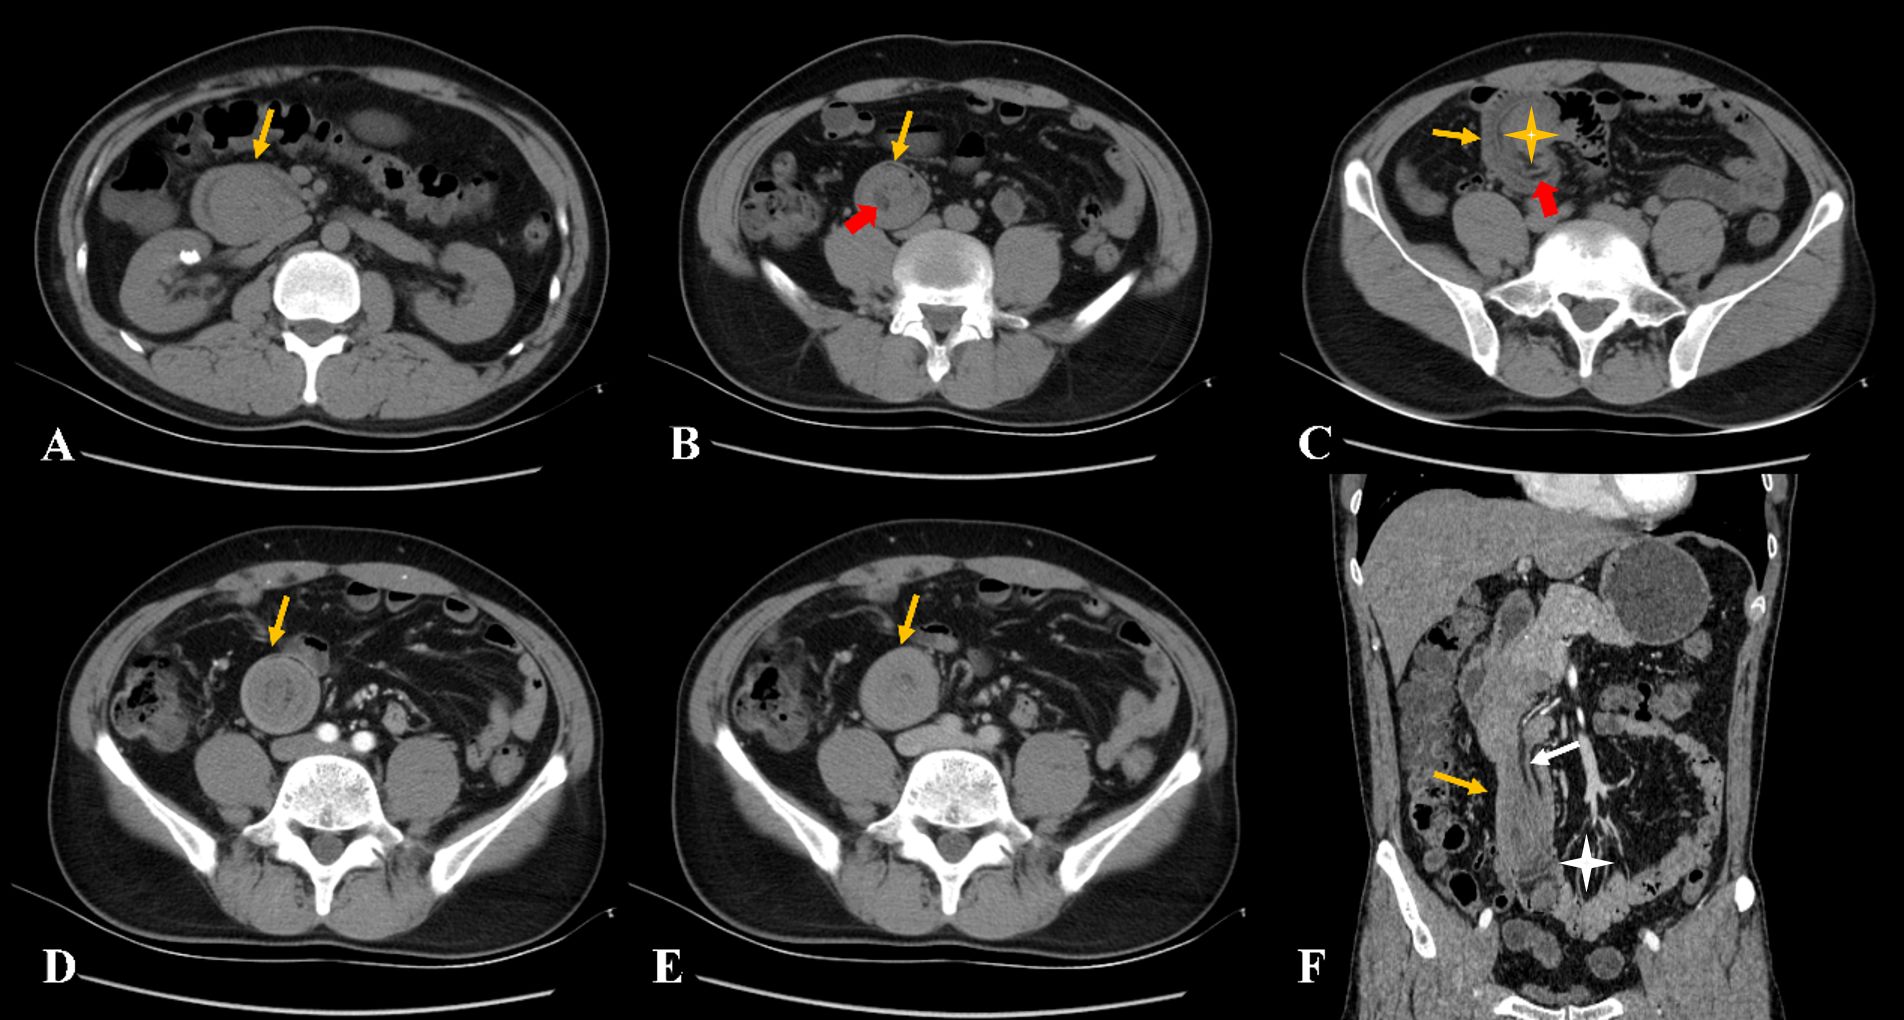

The patient recovered well after surgery. CT demonstrated the resolution of duodenal wall abnormalities with the restoration of normal anatomical position (Figure 4). The current basic situation is good.

Figure 4

CT scan shows two abdominal cross-sections labeled A and B. Yellow arrows point to specific areas on each image, indicating the resolution of duodenal wall abnormalities with the restoration of normal anatomical position.

Figure 4. (A, B) The non-contrast computed tomography showed the resolution of duodenal wall abnormalities with the restoration of normal anatomical position (yellow arrow).